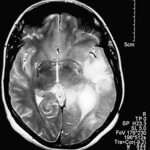

Epigenetic Mechanism Behind The Most Malignant Of All Brain Tumours

Glioblastoma (GBM), the brain cancer better known for having killed Senator Ted Kennedy a few months ago, is the most aggressive and lethal of all brain tumours. But a collaboration between researchers from the University of Minho in Portugal, and the University of California-San Francisco, has found new reasons to be optimist. Their research, published in the journal Cancer Research(1), reveals that activation of a gene called HOXA9 is linked to GBM severity – the more activated HOXA9 is, the more aggressive the tumour turns out to be. The good news is that this activation can be reverted.…

Cancer Initiating Stem Cells Suppress Immune Response To Brain Tumor And The Role Of STAT3 Pathway In Immunosuppression

Cancer-initiating cells that launch glioblastoma multiforme, the mostlethal type of brain tumor, also suppress an immune system attack onthe disease, scientists from The University of Texas M. D. AndersonCancer Center report in a paper featured on the cover of the Jan. 15issue of Clinical Cancer Research.(1) Glioblastoma MuliformeGlioblastoma multiforme (GBM) is the most common and most aggressive of the primary brain tumors. It responds poorly to therapy and glioblastoma multiforme cancer-initiating cellshave been shown to mediate resistance to both chemotherapy and radiation. The current…